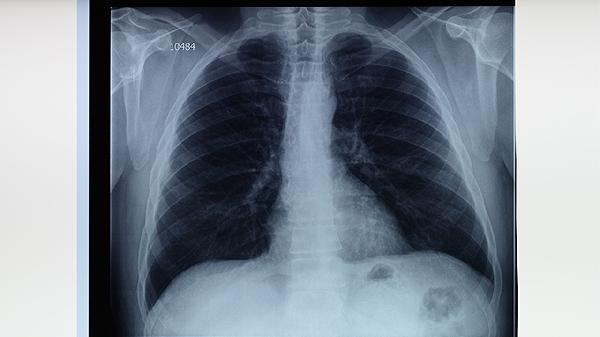

2、胸痛和呼吸困难可能伴随病情加重。肺部感染导致组织损伤和炎症,引起胸痛。随着病情进展,肺功能受损,患者可能出现呼吸急促或困难,尤其在活动后更为明显。

5、咯血是病情严重的信号。当肺部组织受到严重破坏时,可能出现咯血症状,需要立即就医。咯血可能提示肺部血管受损或感染加重,需紧急处理。